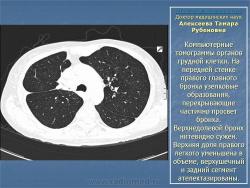

Доктор медицинских наук  Алексеева Тамара Рубеновна

Туберкулез внутригрудных лимфатических узлов.